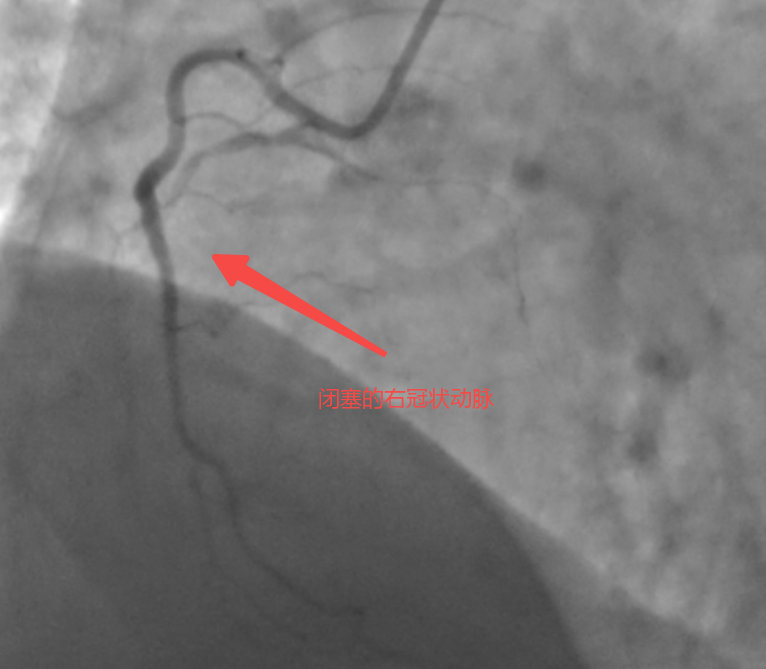

57歲的患者張先生(化名)近1年以來反復(fù)出現(xiàn)胸悶癥狀,經(jīng)當(dāng)?shù)蒯t(yī)院檢查后被診斷為“慢性完全閉塞病變(CTO)”,心臟處三根大血管發(fā)生嚴(yán)重病變,其中很重要的一根血管(右冠脈)完全堵死,還長滿“硬石頭”般的鈣化斑塊。當(dāng)?shù)蒯t(yī)院反復(fù)嘗試介入治療,均未成功打通血管,且評(píng)估認(rèn)為開胸搭橋的效果也不理想。不愿意接受開胸手術(shù)的張先生,慕名來到泰康同濟(jì)(武漢)醫(yī)院心血管內(nèi)科就診。

術(shù)中,馬志強(qiáng)主任團(tuán)隊(duì)啟用三維冠脈造影精準(zhǔn)定位側(cè)支路徑,以頭發(fā)絲般纖細(xì)的導(dǎo)絲,在側(cè)支血管中實(shí)現(xiàn)“毫米級(jí)”推進(jìn),成功建立逆向通路。隨后通過多項(xiàng)正向、逆向技術(shù)成功打通血管并植入藥物支架,恢復(fù)右冠脈血流。術(shù)后患者胸悶癥狀緩解,次日即可下床活動(dòng),目前已順利出院。